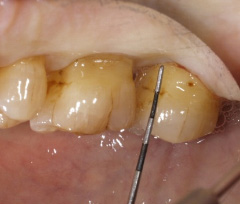

| 深い虫歯のケースでは、切除療法を行い虫歯を取り除き、健全な歯質を歯肉の上に出し、歯肉の盛り上がりを数ヶ月待ってから歯型をとります。 |

||

| 一見分りませんが、かなり歯周病が進行していました。歯周ポケットの改善や歯槽骨を平坦にして清掃しやすい環境を整えます。数ヶ月、歯肉の盛り上がりを待ってから適合の良いクラウンを被せます。 | ||